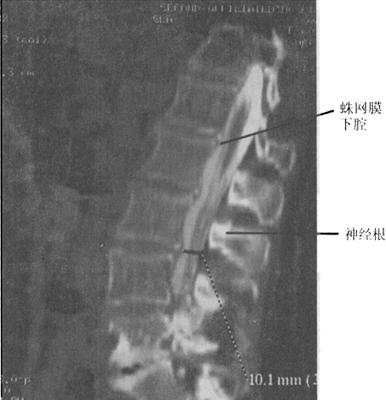

(四)CT脊髓造影或脊髓造影后CT

CT与MR出现以来,脊髓造影已不再常规使用。但在复杂的脊柱损伤CT扫描中,无法显示硬膜囊内结构,使用水溶性非离子型鞘内造影剂进行脊髓造影后CT扫描(CTM)扩展了CT在脊髓损伤中的应用(图7-11)。

图7-11 脊髓造影后多排螺旋CT扫描矢状面重建,可区分脊髓、神经根。蛛网膜下腔充满造影剂呈高密度,而脊髓、神经根呈中等密度

当脊髓、马尾神经被软组织压迫或怀疑硬脊膜撕裂时,CTM扫描就显得特别有用。一般来说,鞘内注射造影剂是通过C1~C2穿刺,以减少搬动病人所带来的潜在损伤。CTM的优点在于:①脊髓更好地显影;②提高软组织损伤压迫脊髓的诊断显示率,例如椎间盘突出或硬膜外血肿;③脊髓神经根的硬膜撕裂的诊断。CTM较之传统X线体层摄影、脊髓造影和CT平扫在脊椎骨折损伤的神经定位方面有较大的优越性。脊髓压迫可以在X线脊髓造影中显示,但在CTM中显示更清楚直观。在严重压迫的情况下,髓内创伤的诊断是非常困难的。硬膜外不同程度的压迫可导致脊髓不同程度的破裂。当造影剂充盈硬膜囊时,严重的脊髓损伤可出现脊髓缺损的征象。硬膜撕裂可导致造影剂外渗至硬膜外间隙。尽管撕裂的硬膜可自愈,但识别硬膜撕裂也是很重要的,因为撕裂可能导致多种后遗症,如脑膜炎、神经根内陷,脑脊膜突出或延迟神经损伤。CTM在全脊髓损伤病人诊断中的作用仍存在争议。

(3)创伤性蛛网膜囊肿:创伤性蛛网膜囊肿是由于脊柱创伤引起脊膜撕裂脑脊液外漏积聚造成,可对脊髓造成压迫性改变。囊肿在T1WI、T2WI呈脑脊液样信号,边界清楚,呈单囊或多囊状改变(图7-20)。

(4)脊髓瘘管形成:脊髓内软化灶形成空洞与相邻的蛛网膜下腔相通,在T2WI上可显示高信号的脑脊液连接于蛛网膜下腔与髓内空洞。